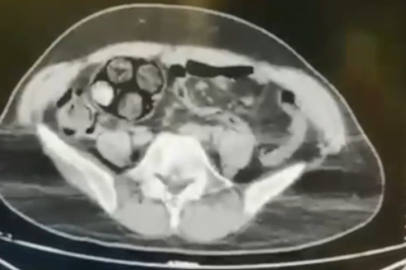

Edinilen bilgiye göre, Artvin İl Jandarma KOM Şube Müdürlüğü ekipleri, İran uyruklu Farshid Rafıeıeınsheykh (43) adlı şüphelinin 8 Mart tarihinde vücudu içerisine uyuşturucu madde gizleyerek Artvin’e getireceği bilgisi üzerine çalışma başlattı. Yapılan takip sonucu Artvin merkez Çayağzı Mahallesi’nde yakalanan şüphelinin üst aramasında herhangi bir suç unsuruna rastlanmadı. Bunun üzerine şüpheli, Ceza Muhakemesi Kanunu'nun 75. maddesi gereği iç ve dış beden muayenesi için Artvin Devlet Hastanesine sevk edildi. Çekilen tomografi sonucu zanlının bağırsaklarında 10 paket tespit edildi. Cerrahi müdahale ile çıkarılan paketlerin içinde toplamda 350 gram metamfetamin maddesi olduğu belirlendi. Gözaltına alınan İranlı zanlı hastanede müşahede altına alınırken, olayla ilgili soruşturma başlatıldı.

Zanlının hastaneden taburcu olmasının ardından hakim karşısına çıkarılacağı bildirildi.